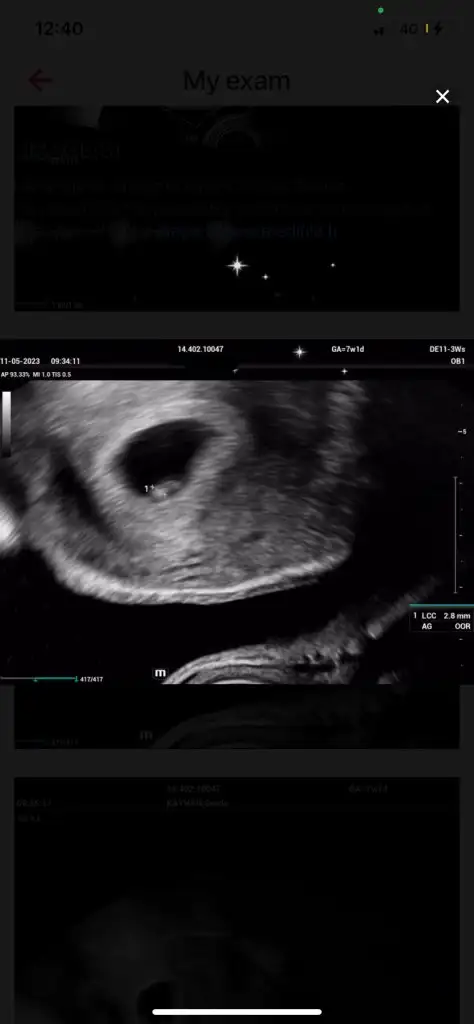

Acillll yolk sac

Yurt dışında yaşıyoruz. Dilimiz çok olmadığı için anlaşamıyoruz da. Doktor kesenin boyutu için iyi dedi. Bebek çok çok çok küçük olduğu için görünmüyor. Haftaya gelin dedi. Yolk sac hakkında bsey konuşmadık.

O resimde solda bsey olması umut oldu bana ama diğer resimde neden yok acaba?

Önce karından baktı. Aynı bu şekilde göründü. Bebeği göremeyince vajinal baktı. Aynı şekilde göründü. Değişen bsey olmadı

Resimlerden birinde bende gördüm ama diğerlerinde olmaması doktorun ultrason cihazını tutuş şeklinden ve fotoğrafi cekisinden değişkenlik gösteriyor olabilir. Yani hafif sağ yapınca görünen yolk kesesi biraz soldan tutunca görünmüyor olabilir neticede çok küçük henüz. Umarım sizde diğer arkadaş ta bundan 5 ay sonra bugunlerinizi düşünüp nekadar stres yaptığınızı her hareketinde bebisinizin sizinle olduğunu çok net hissedip gulumsersiniz ❤️

Merhaba, yolk sac varsa boş gebelik olmaz. Yani şöyle ki önce kese sonra yolk sac kesesi sonra da içinde bebek ve kalp atışı görünür. Eğer geç dollenmeyse bebek ve kalp atışı da buna bağlı geç görünür. Yada embriyo dollenmesinde kromozomlardan biri eksik geliştiyse embriyo oluşumunu durdurur gelişmez neticede düşük olur. Hemen stres yapmayın geç dollenme olma ihtimali yüksek biraz daha sabırla bekleyin Rabbım sağlıkla kucağınıza almayı nasip etsin.

Çok teşekkür ederim, resimde tektaş görüntüsü ufak da olsa var gibi geliyor bana sizce de öyle mi yoksa kafamdan mı uyduruyorum 😕 amiin inşallah içimi rahatlattınız, sağolun🤎